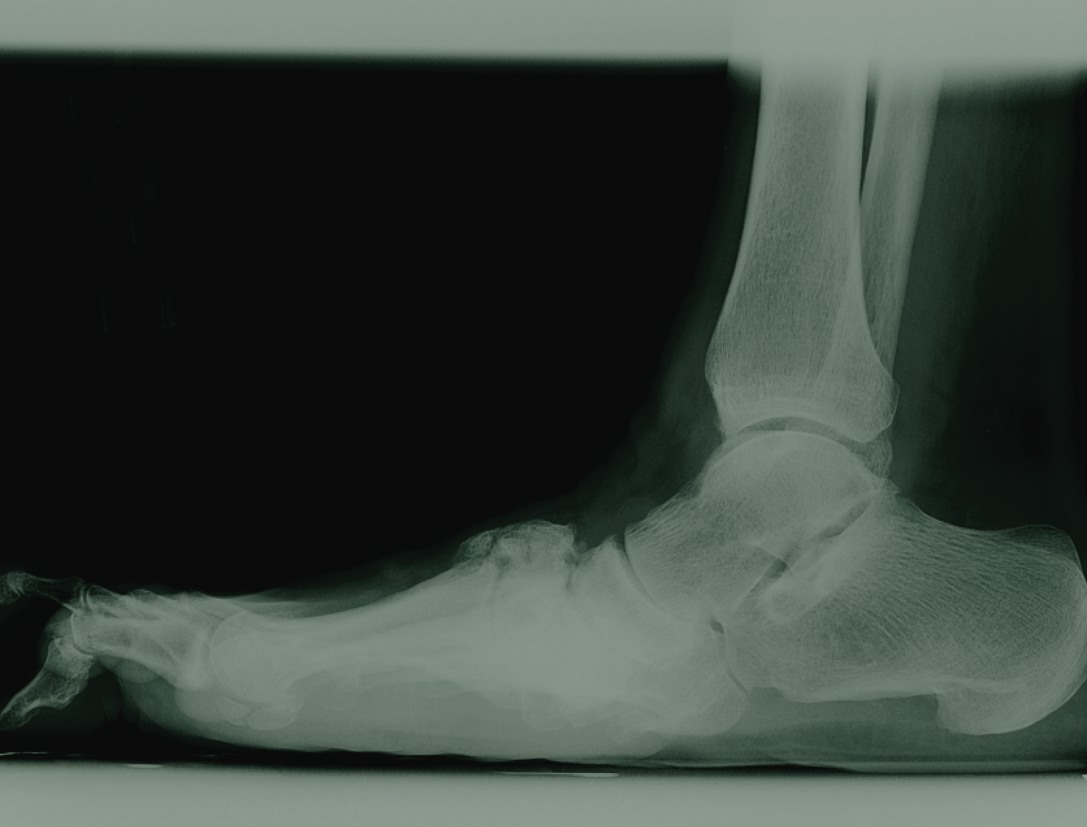

When clinicians diagnose Charcot neuroarthropathy early and treat it appropriately, the majority of patients do well with conservative treatment. They will be left with feet that are free of ulcerations and have minimal residual deformities. Employing protective shoes or braces can help prevent the severe consequences of the neglected or misdiagnosed Charcot joint. Unfortunately, a large number of patients will present with foot deformities, instability or ulcerations as their initial symptoms. For those patients, one can consider a variety of surgical options, which range from simple exostectomies to exostectomies with rotational flaps or even free tissue transfers. In more severe deformities with significant instability, primary fusion may be the procedure of choice. The level of the deformity will dictate the level of fusion whether it is a midfoot, triple or ankle arthrodesis. Today, the use of plates, screws and intramedullary nails has become standard practice in these complex fusions. They provide more solid fixation with improved outcomes. Cannulated screws facilitate relatively simple insertion. In recent years, the use of external fixation has become more commonplace. These devices have undergone significant changes since their introduction into surgical practice in the late 1800s. Circular frames with skinny wires have replaced the unirail with Schanz pin systems for the most part. Additionally, these circular frames can either be static or dynamic depending on the goals of the surgeon. Internal and external fixation play key roles in reconstructive surgery of the Charcot foot and ankle. Understanding the indications for these modalities will allow for more successful outcomes and fewer complications.

Internal fixation is best suited for subluxed joints with minimal bony destruction. Good bone quality and substance are essential for screw purchase. It is also preferable to place screws where an intact soft tissue envelope exists. This implies that whenever possible, it is best to perform surgery when plantar ulcerations are healed. Also be aware that the presence of unresectable osteomyelitis is a contraindication when it comes to using internal fixation. Nevertheless, internal fixation maintains clear advantages over external fixation in that it facilitates compression across joints and buried fixation devices with a single operative procedure.